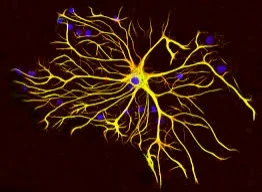

Multiple sclerosis (MS) affects approximately 2.5 million globally yet is a poorly understood autoimmune condition in the medical community. Each week, it’s estimated that over 200 Americans are diagnosed with multiple sclerosis. This debilitating condition occurs when the immune system attacks myelin, a coating that surrounds the nerves of the brain and spinal cord.

Nutrient status and MS are strongly correlated. Vitamins such as cobalamin (B12), pantothenate (B5), riboflavin (B2), Vitamin K are required for production of myelin. Deficiencies in these nutrients are correlated with multiple sclerosis and can be confirmed by laboratory testing. Functional medicine takes all of these factors into account in order to identify and treat the root cause. Improvement in symptoms can be experienced and prevention of progression of the disease.